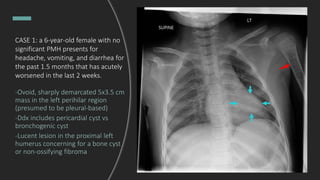

CASE 1: a 6-year-old female with

no significant PMH presents for

headache, vomiting, and diarrhea

for the past 1.5 months that has

acutely worsened in the last 2

weeks.

What do you see?

CASE 1: a 6-year-old female with no

significant PMH presents for

headache, vomiting, and diarrhea for

the past 1.5 months that has acutely

worsened in the last 2 weeks.

-Ovoid, sharply demarcated 5x3.5 cm

mass in the left perihilar region

(presumed to be pleural-based)

-Ddx includes pericardial cyst vs

bronchogenic cyst

-Lucent lesion in the proximal left

humerus concerning for a bone cyst

or non-ossifying fibroma